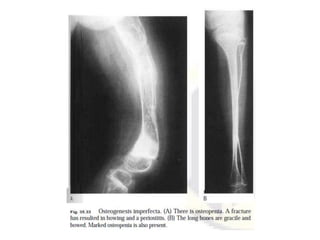

Radiographic features

Radiographic features vary according to the type

of disease and its severity and include

osteopenia and fractures, which may heal with

florid callus formation, mimicking

osteosarcoma.

Bones are thin and under-tubulated (gracile),

normal in length or shortened, thickened and

deformed by multiple fractures.

Intra-sutural (Wormian) bones can be identified

on skull radiographs.

OI Diagnosis-Plane radiography

32

Obtain a radiographic skeletal survey after birth.

Generalized osteoporosis is present

In milder forms (Types I & IV)–Thin and gracile bones

with thin cortices. Skull vault may be normal.

In the more severe forms (types 2 and 3)-The bones

are thick and short with multiple fractures and

hyperplastic callus formation.

The skull is osteopenic and multiple wormian bones

are present. Multiple rib fractures may cause the bones

to become broad and deformed.

Platyspondyly and scoliosis are often present

Osteogenesis imperfecta. Results from genetic

mutations causing abnormalities in Type I collagen, and

resulting in osteoporosis and low-trauma fractures

(brittle bone disease). The different types vary in clinical

presentation and severity.

Frontal view of the femora in an infant showing reduced

bone density and marked deformity due to multiple